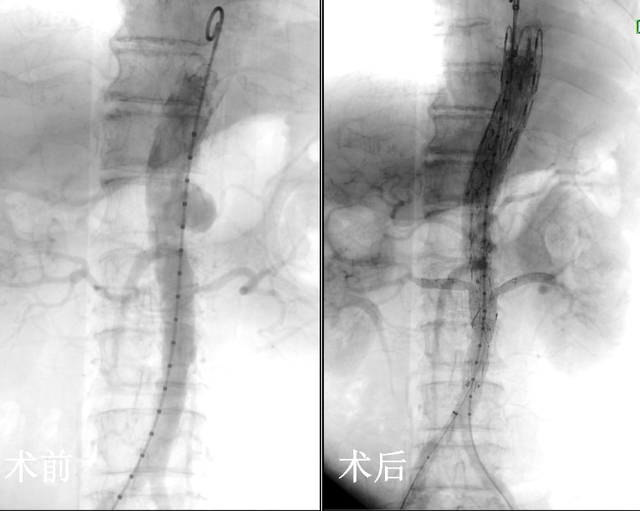

∩0∩ 7cm腹主动脉夹层动脉瘤,危!国际尖端“开窗”技术让七旬患者转危为安医师报讯(通讯员 方志宏 杨霜)近日,69岁的韩娭毑由于左侧肱骨骨折在外院住院治疗。住院期间,行腹部彩超检查发现了腹主动脉夹层动脉瘤,瘤体直径接近7cm(正常血管直径2cm左右,已超正常血管三倍,破裂几率高达60%-80%),且伴随明显腹痛,需要尽快手术治疗。韩娭毑家人多方求医,了...

重获“心”生 株洲市人民医院为主动脉夹层患者打通“生命线”成功地为70岁的潘奶奶施行了主动脉覆膜支架植入术,使其转危为安,术后潘奶奶恢复良好,重获“心”生。几天前,家住荷塘区的潘奶奶因胸腹痛4小时由家人送至基层医院,诊断考虑主动脉夹层,危急情况之下基层医院立即启动市人民医院胸痛中心并转院治疗,诊断为主动脉夹层(B型)。这一...

先健科技现涨超7% 主动脉弓支架系统获国家药监局正式注册批准中国医学科学院阜外医院舒畅教授与集团共同研发的主动脉弓支架系统获中国国家药品监督管理局正式注册批准。该产品为国家药品监督管理局批准的首款明确针对使用开窗技术进行主动脉弓部分支重建的覆膜支架系统,适用于Stanford B型主动脉夹层患者的腔内修复治疗,可在修复主...